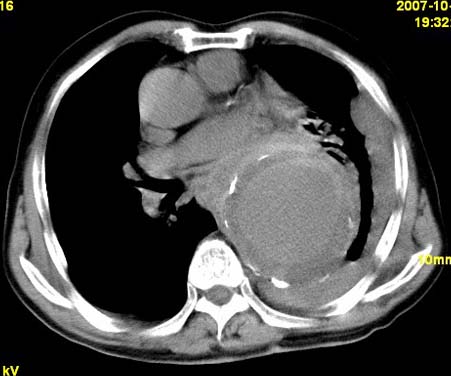

标题: CT10190:男,70,胸部疼痛数年,加重一天。典型病例。 [打印本页]

标题: CT10190:男,70,胸部疼痛数年,加重一天。典型病例。

典型降主动脉瘤伴血栓形成.瘤体下部局部边缘不清,结合病史,不除外局部撕裂外渗可能.另左侧胸水,肺部压迫不张改变.建议增强进一步检查.

典型降主动脉瘤伴血栓形成。支持:降主动脉瘤!

考虑胸主动脉瘤并血栓形成,胸腔积液

1.降主动脉瘤伴血栓形成.2.左侧胸腔积液,考虑为主动脉瘤破裂所致。

降主动脉明显增粗,边缘模糊,周围低密度影,双侧胸膜腔少量积液,结合临床考虑胸主动脉瘤破裂并双侧胸腔积液。